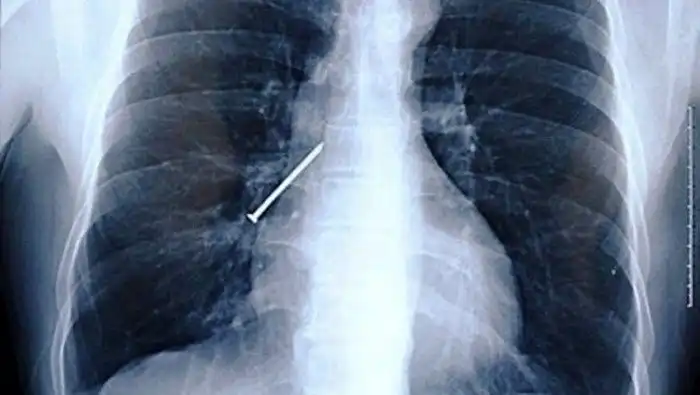

Забитые крылышки

Не до шуток было жителю Британии, которой перекусил в кафе и обнаружил в курином крылышке гвоздь. Он незамедлительно обратился за медицинской помощью, и выяснилось, что еще один гвоздь мужчина успел проглотить. К счастью, все обошлось без последствий.